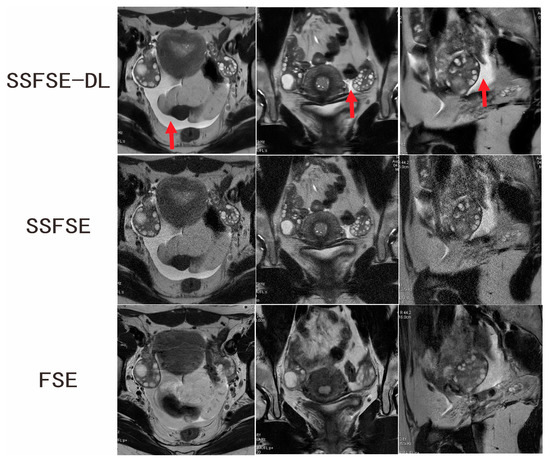

Two independent observers conducted the subjective assessment on a total of 40 ovaries in 60 images. Table 1 summarizes the comparison results of the qualitative image analyses between SSFSE-DL and SSFSE as well as between SSFSE-DL and FSE for each observer. Each subjective evaluation item was presented as mean ± SD. Significantly better scores of the blurring artifacts, subjective noise, and clarity of the follicles rated by observers were found between SSFSE-DL and SSFSE (p < 0.05) as well as FSE (p < 0.05). The use of SSFSE helped to reduce the blurring artifacts compared to the FSE sequences, and the application of DL reconstruction helped to reduce the noise of the high-resolution SSFSE images. Two typical cases are shown in Figure 1 and Figure 2. The inter-observer agreements of the three subjective aspects were good for SSFSE-DL (Kappa = 0.671–0.789), moderate to good for SSFSE (Kappa = 0.580–0.636), and FSE (Kappa = 0.474–0.664).

Figure 1.

Ovarian MRI in a 16-year-old adolescent girl with confirmed PCOS. SSFSE-DL images (upper row) show the lowest noise, blurring artifacts, and the bilateral enlarged ovaries with a dominant follicle and many small follicles. The pelvic fluid collection (arrow) is easily detected on the SSFSE-DL images. Noise is prominent on the SSFSE images (middle row). The FSE images (lower row) mainly showed blurring artifacts caused by respiratory and bowel motility.

Figure 2.

Ovarian MRI in a 28-year-old woman with confirmed PCOS. SSFSE-DL images (upper row) show the least noise and blurring artifacts. The bilateral enlarged ovaries with many small peripheral follicles are clearly delineated on the SSFSE-DL images. The display of the follicles is impaired by the noise on the SSFSE images (middle row) and by the blurring artifacts in the FSE images (lower row).